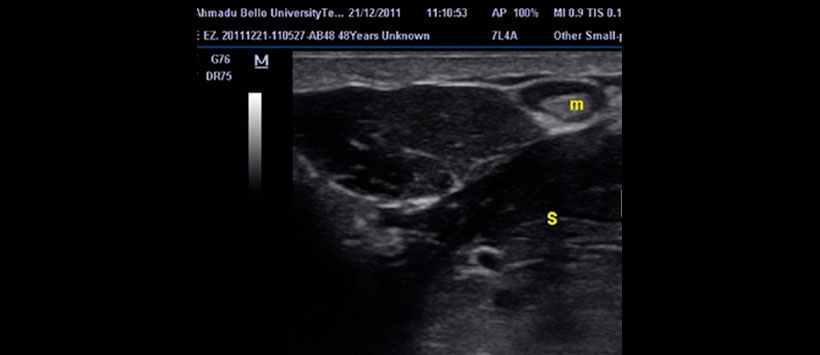

Figura 2: Ultrasonido submandibular izquierdo que muestra una masa ovalada brillante (m) de forma ovalada que proyecta sombras acústicas posteriores en el conducto izquierdo de Wharton rodeado de líquido anecoico (saliva). (imagen original)